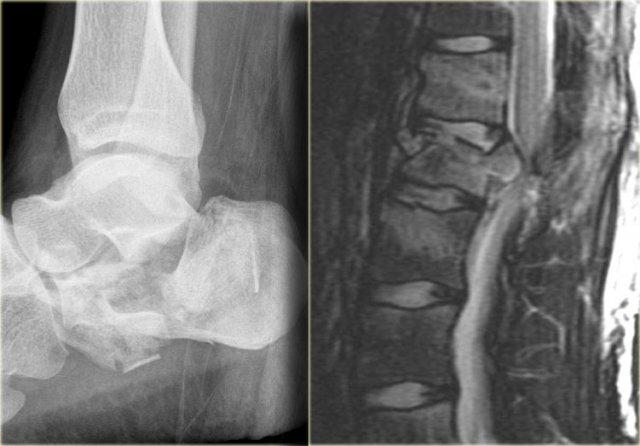

Bên trái là hình ảnh gãy xương gót và gãy cột sống thắt lưng.

Đây được gọi là ‘gãy xương của người nhảy’ hoặc ‘gãy xương của người tình’, vì thường gặp ở những người nhảy qua cửa sổ để trốn thoát khỏi cảnh sát hoặc người chồng/vợ ghen tuông.

Trong trường hợp này, rõ ràng chúng ta đang nhìn vào một gãy xương không vững, vì đây là gãy xương vỡ tung.

Cả cột trước và cột giữa đều bị tổn thương.

Ngoài ra, có phù nề ở các mô mềm phía sau cho thấy cột sau cũng bị ảnh hưởng.

Cũng cần lưu ý phù nề tủy xương ở các thân đốt sống lân cận do chịu tải trọng dọc trục nghiêm trọng.